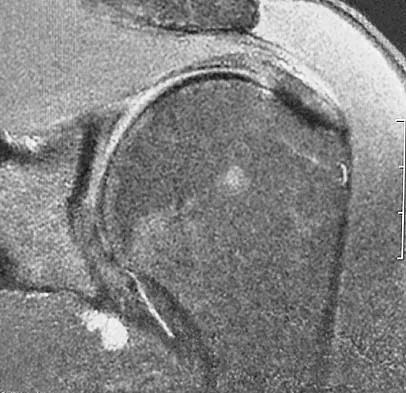

In the arthroscopic photograph shown in Figure 5, the structure labeled "A" functions primarily as a restraint to translation of the humeral head in what direction?

Explanation